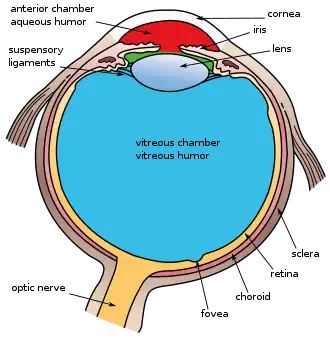

The retina is a thin layer at the back of the eye that processes visual information and sends it to the brain.[5] When the retina detaches, common symptoms include seeing floaters, flashing lights, a dark shadow in vision, and sudden blurry vision.[1][3] The most common type of retinal detachment is rhegmatogenous, which occurs when a tear or hole in the retina lets fluid from the center of the eye get behind it, causing the retina to pull away.[6]

The retina is a thin layer of tissue located at the back of the eye.[1][5] It processes visual information and transmits it to the brain.[5] Retinal detachment occurs when the retina separates from the layers underneath it.[2] This impairs its function, potentially leading to vision loss.[2][4] Retinal detachment often requires urgent medical intervention to prevent permanent vision loss.[3]

- Rhegmatogenous retinal detachment is caused by a tear or break in the retina.[6][9] This allows vitreous humor, the fluid that normally sits in the center of the eye, to build up behind the retina.[6][9] As a result, the retina can eventually separate from the tissues underneath it.[6][9][10] This is the most common type of retinal detachment.[6]

- Tractional retinal detachment occurs when scar tissue on the retina exerts a pulling force, leading to detachment.[6][10] This is occurs in the absence of retinal tears or breaks and is most commonly associated with abnormal blood vessel growth due to proliferative diabetic retinopathy.[6][9][10] Other causes include trauma, retinal vein occlusion, sickle cell retinopathy, and retinopathy of prematurity.[8][9][10][11]

- Exudative retinal detachment occurs when fluid accumulates beneath the retina, causing it to detach.[6][10][11] This occurs in the absence of retinal tears or breaks. Common causes include age-related macular degeneration, inflammatory diseases, ocular tumors, and injuries to the eye.[6][9][10][11]